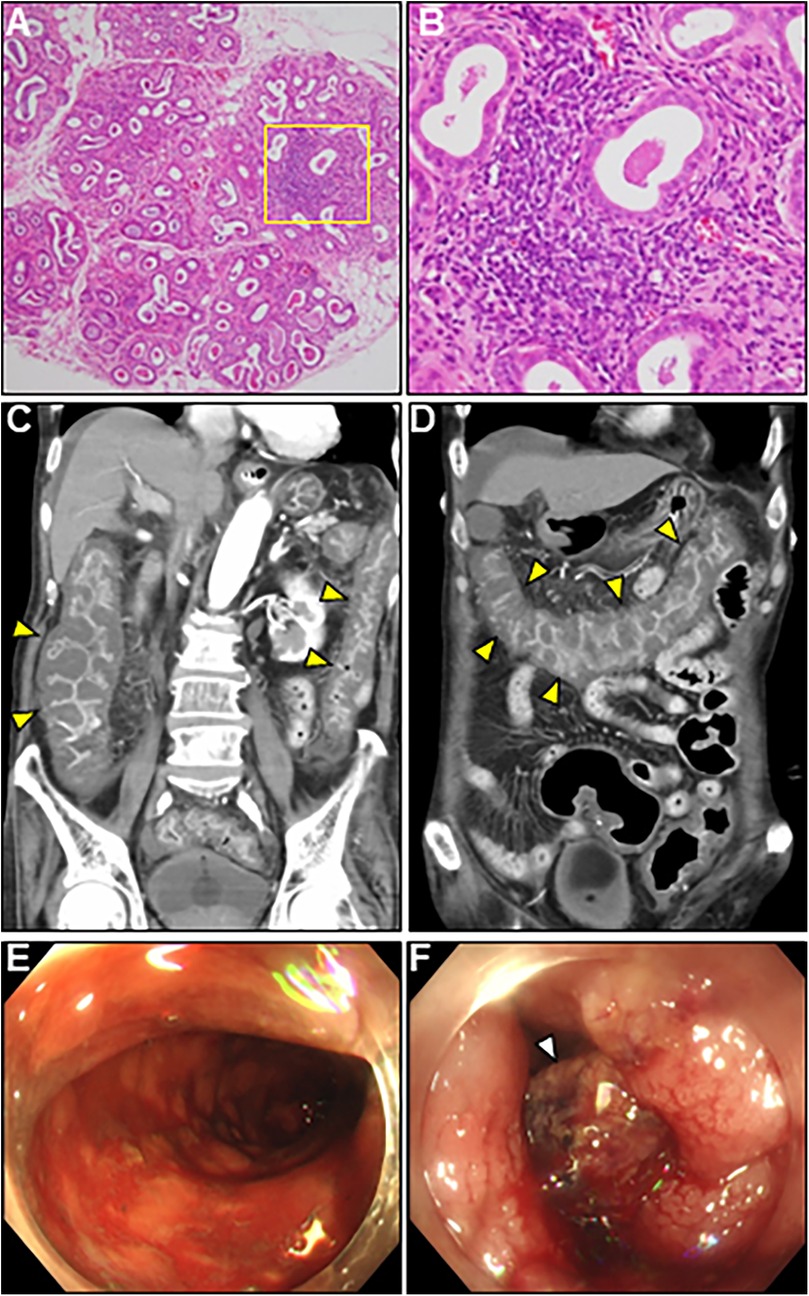

A comprehensive diagnostic evaluation of eosinophilia, including eosinophilic granulomatosis with polyangiitis, hypereosinophilic syndrome, parasitic infections, and hematological malignancies, revealed negative results. Viral screening using paired serology for virus antibody titers was unremarkable (Supplementary Table S1). In addition, a workup for the unexplained eosinophilia was performed. Most importantly, a renewed interview with the patient's family revealed that the patient complained of oral dryness for >6 months and frequently drank too much liquid. We performed serologic testing for underlying systemic autoimmunity using stored blood samples obtained on admission. Strikingly, serologic testing using pre-corticosteroid treatment sera on admission demonstrated strong positivity for anti-SS-A and anti-SS-B antibodies (469 and 199 U/ml, respectively), strongly suggesting SS. Elevated levels of serum rheumatoid factor (31 IU/ml, normal: < 15 IU/ml), interleukin (IL)-4 (36.5 pg/ml, normal: < 3.9 pg/ml), IL-5 (50.9 pg/ml, normal: < 3.9 pg/ml), and antinuclear antibody titer (1:320) were also noted. Brain CT revealed fatty changes in the bilateral parotid glands. An abnormal Schirmer's test result and lip biopsy of the patient revealed focal lymphocytic sialadenitis with a focus score of ≥1 focus/4 mm2, meeting the 2016 ACR/EULAR classification criteria for pSS (4) (Figures 4A,B). Based on the above, the final diagnosis of AEM associated with pSS was established. On day 22, the patient showed an evident improvement in cardiac functional and structural abnormalities, as well as electrocardiographic findings, except for an LV apical aneurysm (Figures 2G,H; Supplementary Video S3, and S4). A follow-up brain MRI demonstrated complete recovery of AOM. Thereafter, the patient received a maintenance dose of prednisolone (20 mg/day) and underwent cardiac rehabilitation. The post-treatment course of the patient was complicated by digestive involvement (DI) including esophageal candidiasis and chronic atrophic gastritis. Accordingly, oral miconazole and a reduced dose of prednisone (10 mg/day) were prescribed. On day 51, the patient experienced three episodes of bloody stools, and the anticoagulant was discontinued. On day 52, the patient experienced hemorrhagic shock due to lower gastrointestinal bleeding with progressively impaired consciousness, necessitating tracheal intubation, catecholamine administration, frequent blood transfusions, and careful monitoring in the ICU. Enhanced CT showed diffuse, severe, and edematous thickening of the entire colonic wall despite intact mesenteric arterial circulation (Figures 4C,D). Colonoscopy revealed diffuse edematous mucosa, complete loss of vascular pattern, mucosal friability, and multiple superficial ulcers with contact bleeding in the rectum and sigmoid colon (Figures 4E,F). These lesions were observed in continuity with the rectum. Given the patient's underlying condition of pSS, CT and colonoscopy findings suggestive of ulcerative colitis (UC), the rapidly progressive course, and steroid resistance, fulminant UC was strongly suspected. However, we could not perform colon biopsies due to the rapid deterioration of the patient's condition. Despite intensive therapy, the patient eventually succumbed to septic shock on day 59. An autopsy of the patient was not performed because of the refusal by family members. We present a summarized illustration of the case presentation in Supplementary Figure S1.

Figure 4. Lip gland histopathology, computed tomography (CT) and colonoscopy findings. (A) Pathology of a minor salivary gland biopsy (20× magnification). (B) Magnified view of the box in (A) at 40×. Hematoxylin and eosin staining showing focal lymphocytic sialadenitis with periductular aggregates of >50 lymphocytes. (C,D) Coronal enhanced CT revealing whole and homogeneous large bowel wall thickening characterized by submucosal edema and mucosal thickening with the disappearance of the haustral folds (arrowheads). Note the intact small bowel. (E,F) Colonoscopy revealed continuous diffuse mucosal inflammation from the rectum to the transverse colon. There are no vascular patterns, multiple ulcers with friability, mucosal desquamation (arrowhead), or contact bleeding.